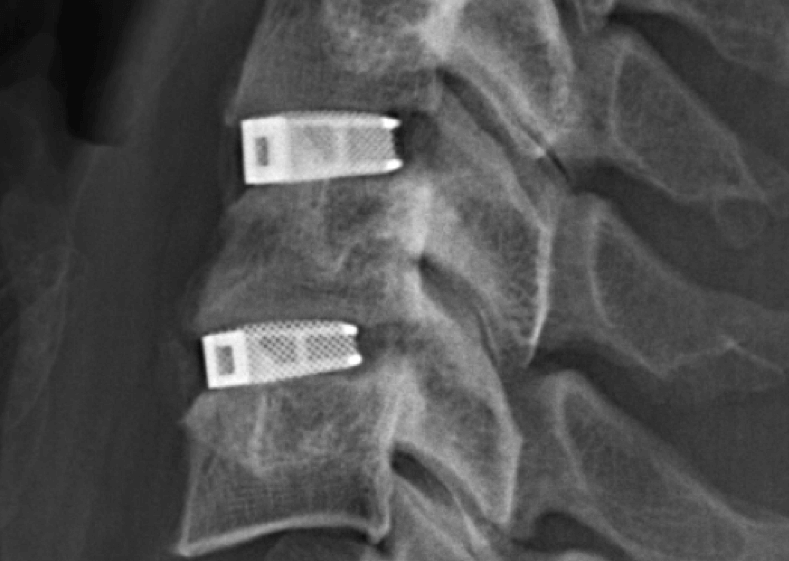

Entwickelt wurde der Multilevel-Zervixkäfig, unter Verwendung der Marke Cellular Titanium®, von der Emerging Implant Technologies GmbH (EIT), mit Sitz im Medizintechnikcluster Tuttlingen in Baden Württemberg, berichtet das Unternehmen. Die Käfige werden mit dem 3D-Druckverfahren Selektives Laserschmelzen (SLM) gedruckt. Indem EIT die Laserbewegungen präzise programmiert, entsteht ein Kern, der die spongiöse („schwammige“) und kortikale („harte“) Struktur des Knochens nachahmt. Im Körper sorgt die biomimetrische gitterartige Struktur dafür, dass das Gewebe durch das Zentrum wächst und gebrochene Knochenstücke wieder zusammenfügt.

Das EIT Cerviximplantat ist von bemerkenswerter Qualität. Es handelt sich um ein 3D-gedrucktes Gerät, das über sieben Ebenen der Beschädigung der Wirbelsäule angebracht werden kann.

In Anlehnung an die internationale Tabelle für Rückenmarksverletzungen kann das Zervikalimplantat des EIT in den Ebenen C2 bis T / Th1 für die mittleren und oberen Segmente der Wirbelsäule eingesetzt werden. In der oberen Ebene (C2) kann das Implantat zur Behandlung von Verletzungen der Hörnerven, der Nebenhöhlen, der Augen und der Zunge verwendet werden. Die unteren Ebenen umfassen Schultern, Nacken, Ellbogen, Arme und Finger.